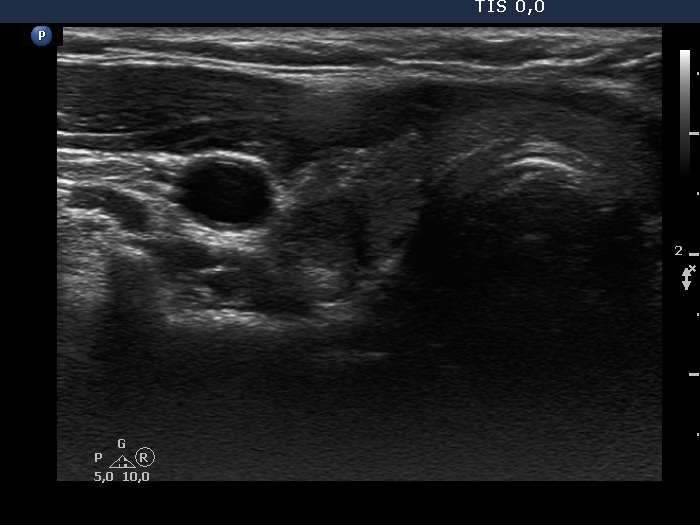

Consecutive patients with Hashimoto's thyroiditis - Case 13. (ultrasonographic picture 2)

Lower part of the right lobe, horizontal scan. There is a more hypoechogenic area in the dorsolateral part of the thyroid.